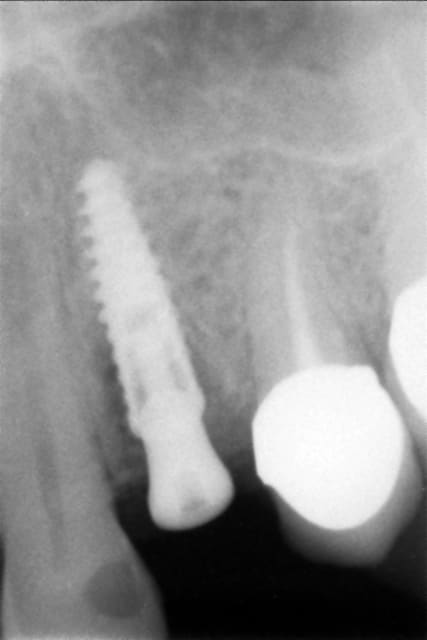

Bon mon numéro 3 est plus énigmatique.

Patient 37 ans, pas de souci médical, perf de racine distale de 47 par tenon radiculaire...

- Extraction le 5/05/10

- Alvéolite suppurée, traitement par mèches eugenol

- à j+7, mise en place d'ALVOGYL, car le patient part en vacances

- à 2 mois : je vais pour clouter, le site est toujours plein de fibres d'alvogyl non résorbée...

Bref, je pleure et referme.

- à 6 mois : implantation d'un inkone 5.5/8.5

- période d'ostéointégration : du 30/11 au 30/03 (prudent)

-> fibrointégration

- dépose illico et re-pose à 6 semaines, ça roule aujourd'hui.

Bon, honnêtement, je trouve que je l'avais mal posé, il était pas assez enfoui, et j'avais laissé des remparts osseux trop fins...

Mais bon, on ne peux exclure de me dédouaner en accusant un état de surface, c'est gentil de votre part si vous y penser.